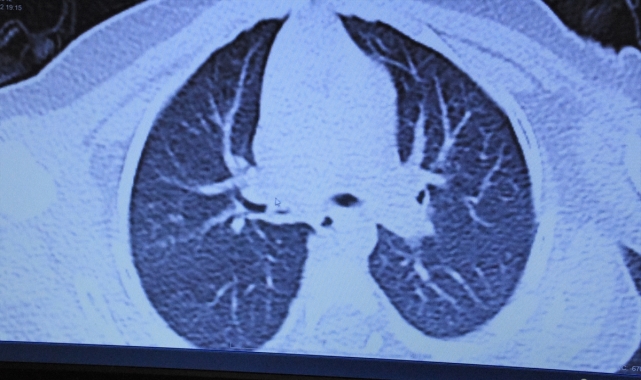

ZEKERİYA KARADAVUT - Aksaray'da morarma, nefes alamama ve öksürük şikayetiyle hastaneye götürülen çocuk, sağ akciğer girişindeki soluk borusunu tıkayan fıstığın çıkarılmasıyla rahat nefes aldı.Merkeze bağlı Karacaören köyündeki evlerinin balkonunda arkadaşlarıyla kuruyemiş yiyen 1,5 yaşındaki Yusuf, aniden rahatsızlandı. Bir süre sonra öksürmeye, morarmaya ve nefes alamamaya başlayan Yusuf'un annesi Gülden Han, çocuğunun boğazına bir şey takıldığını düşündü.Çocuğun sırtına vurarak boğazına kaçan yabancı cismi çıkarmaya çalışan Han, başarılı olamayınca küçük Yusuf'u, Aksaray Eğitim Araştırma Hastanesine götürdü.Burada yapılan detaylı tetkiklerde çocuğun sağ akciğerinin havalanmadığı görüldü.Her geçen dakika aleyhine işleyen çocuk, acil olarak bronkoskopi (kamerayla akciğerlere bakılma işlemi) için hazırlandı. Başarılı işlemin ardından akciğerindeki fıstık çıkarılan Yusuf, rahat nefes almaya başladı, şikayetleri sona erdi.- Dudakları morarmaya başlayınca panik arttıİki çocuk annesi Gülden Han, AA muhabirine, Yusuf'un birden rahatsızlandığını, ağlamaya başladığını söyledi.Çocuğunun nefes almakta güçlük çektiğini görünce kendince bir şeyler yapmaya çalıştığını, ancak başarılı olamadığını belirten Han, şöyle konuştu:"Çok korktum, elim ayağıma dolaştı pek bir şey yapamadım. Ardından oğlum öksürmeye başladı, boğazında hırlama oluştu, rahat nefes alamıyordu. Dudakları falan morarmaya başlayınca Aksaray Eğitim ve Araştırma Hastanesine getirdik. Hemen çocuk cerrahi servisine yönlendirildik. Hocam muayene etti, nefesinde azalma olduğunu bir cisim yutmuş olabileceğini söyledi. Ardından işleme alındı. Allah'a şükür, şimdi yavrumun sağlık durumu çok iyi. Annelere tavsiyem evlerine kuru yemiş tarzında şeyler almamaları."- "Evlerimizde çocuklarımız için koruyucu önlemler almak çok önemli"Aksaray Eğitim ve Araştırma Hastanesi Çocuk Cerrahi Bölümü Uzmanı Dr. Öğretim Üyesi Mustafa Tuşat da küçük Yusuf'un ilk muayenesinde solunum sıkıntısı olduğunu, morarmaların başladığını gözlemlediğini dile getirdi.Yapılan tetkiklerde akciğerin bir kısmını tamamen kapatan yabancı bir cisim gördüklerini anlatan Tuşat, şunları kaydetti:"Hemen yavrumuzu bronkoskopi için ameliyata aldık. Yusuf'un, sağ akciğerini tamamen kapatan fıstığı başarılı şekilde çıkardık. Yavrumuzda herhangi bir komplikasyon oluşmadan ameliyatımızı bitirdik. Yusuf'un durumu gayet iyi. Yabancı cisimlerde erken tanı hayat kurtarıyor. Küçük çocukları olan ailelerin evlerinde kuruyemiş, şeker gibi taneli şeyleri ortalık yerlerde bulundurmaması gerekiyor. Gerekirse çocukları büyüyene kadar kuruyemiş almamalarını tavsiye ediyoruz. Yavrularımızın hayatını tehlikeye atan bir durum söz konusu. Evlerimizde çocuklarımız için koruyucu önlemler almak çok önemli."